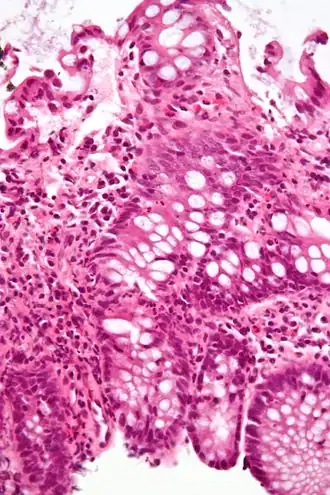

Коли́т (лат. colitis; от греч. kolon — толстая кишка и греч. itis — воспалительный процесс) — воспалительное заболевание слизистой оболочки толстой кишки. Чаще болеют мужчины 40—60 лет и женщины 20—60 лет. Протекает остро или хронически. Считают, что проявления хронического колита имеют место у каждого второго больного с проблемами органов пищеварения. К колитам предрасполагают снижение общей резистентности организма, недостаток растительной клетчатки в пище, воспалительные процессы аноректальной зоны (восходящая инфекция).

Диагноз колита основывается на типичных жалобах, сборе анамнеза (перенесенный гастроэнтероколит, пищевая токсикоинфекция и др.), физикальном обследовании (пальпация живота, пальцевое исследование, аноскопия), инструментальных методах (эндоскопия, ректороманоскопия и ирригоскопия с введением контраста — сульфата бария) и лабораторных данных. Инструментальные методы позволяют визуально контролировать состояние слизистой оболочки, и дифференцировать обычный колит от язвенного колита.